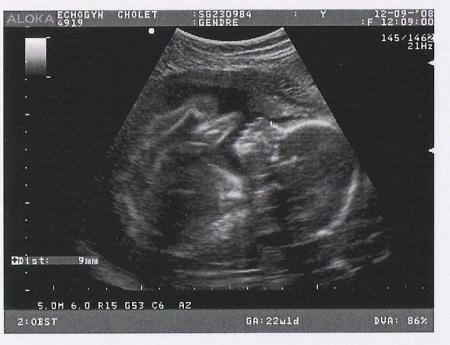

Ca y est, ça c'est fait!

2éme échographie géniale, on a pu voir tous ses petits membres, c'était trop bien...

Nous savons donc désormais que nous allons avoir une petite fille, reste plus qu'à lui trouver un prénom! Mission la plus laborieuse!!!

Nous sommes trés heureux tout les deux...